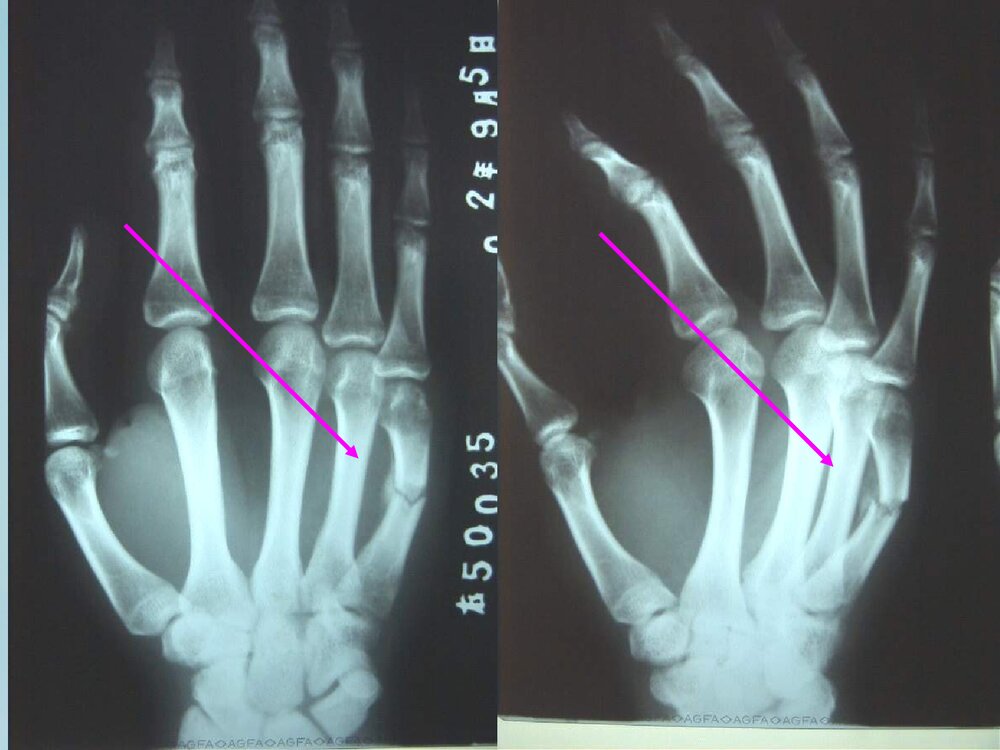

了解掌骨的解剖、病因病理、诊断、整复和夹板固定方法。掌骨有5块,并列成排,按其解剖部位可分为头、颈、干和基底部。掌骨与远排腕骨构成腕掌关节,其中以第1掌骨的腕掌关节最为重要,为拇指的关键性关节,此关节在外展拇长肌牵引下保持于外展伸直位,在内收拇指肌的牵引下,稳定于内收屈曲位,二肌相互拮抗能使拇指“虎口”加大,在腕掌关节稳定的基础上,屈与伸拇长肌可使拇指远端发挥其最有效的功能。第1掌骨短而粗,第2、3掌骨长而细,且较突出,第4、5掌骨既短又细,握拳击物时,重力多落在第2、3掌骨上,故易发生骨折。掌骨骨折多发生在第一掌骨基部1厘米处的骨折,多见于成年人、儿童较少见。骨折近端受拇长展肌的牵拉,向桡侧背侧移位,骨折远段受拇长屈肌及拇内收肌的牵拉,向掌侧尺侧移位,骨折部呈...